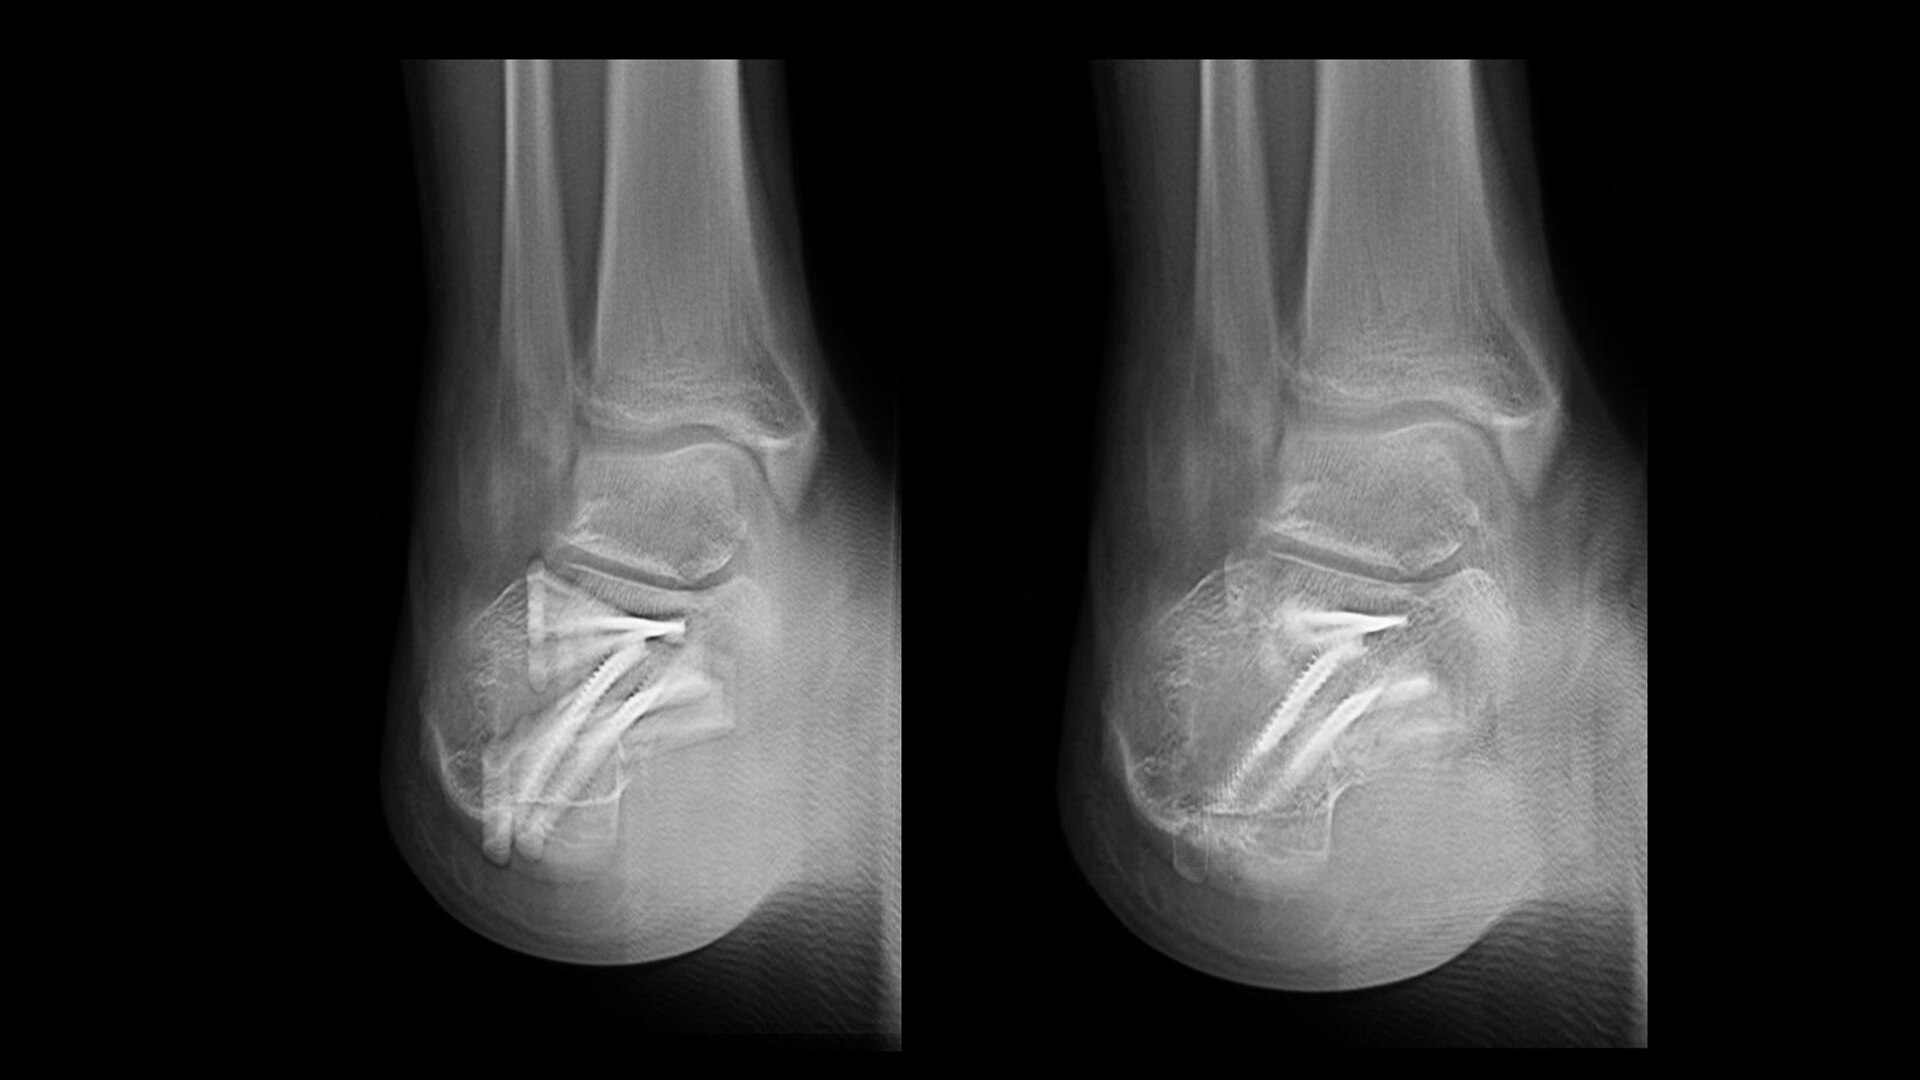

Metal artifact reduction

VolumeRAD Metal Artifact Reduction (MAR) provides quality multi-level image slices even with metal implants

Metallic implants often cause difficulty in digital tomographic imaging. Often black lines appear in the X-ray (an undershoot) or a white ring appears around the metal or there is streaking throughout the image. VolumeRAD Metal Artifact Reduction removes these effects, improving visibility, enabling analysis of implant placements and increasing clinical confidence.

Image caption: Wrist fracture with metal implant | Conventional (left) vs. VolumeRAD with Metal Artifact Reduction (right)